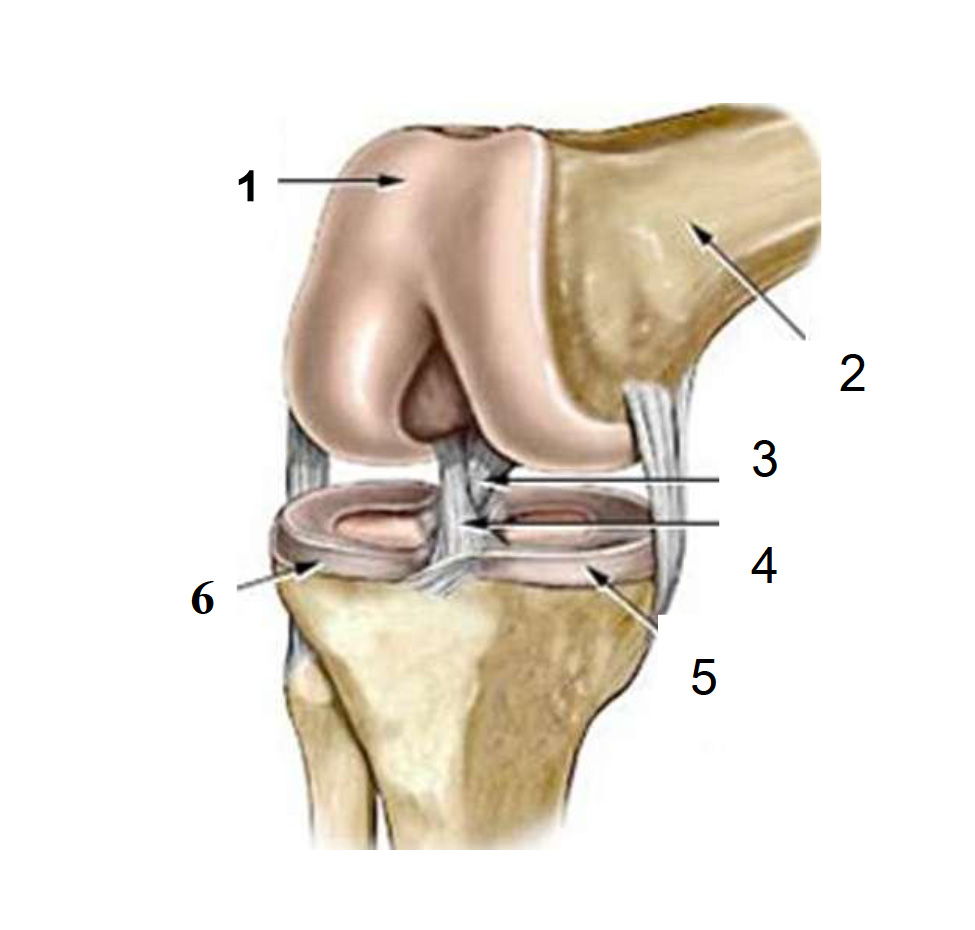

Анатомические изображения менисков и коленного сустава

Раздел: Иллюстрированные советы